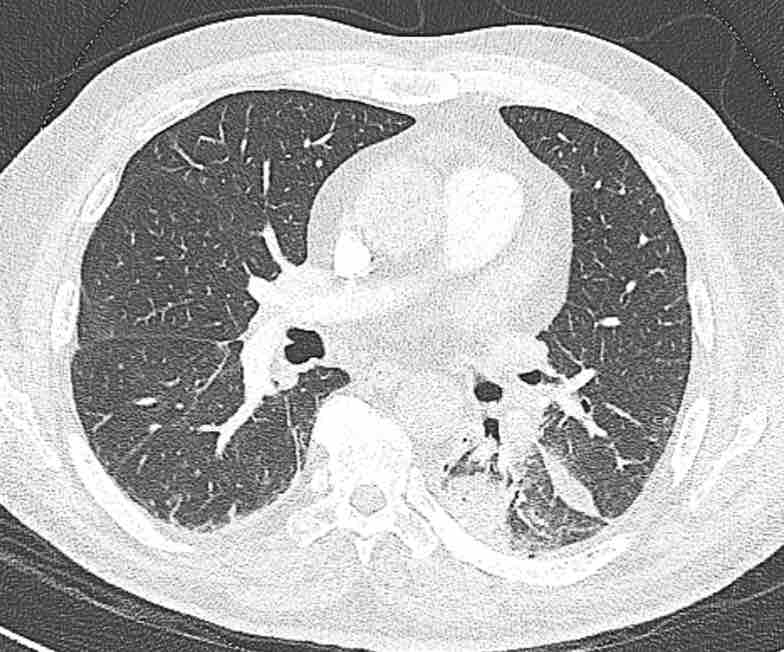

Cuộn qua các hình ảnh để quan sát khí quản phân chia thành phế quản chính phải và trái, sau đó tiếp tục phân chia thành các phế quản thùy và phế quản phân thùy.

Cuộn qua các hình ảnh để quan sát cách phổi được phân chia thành các phân thùy.